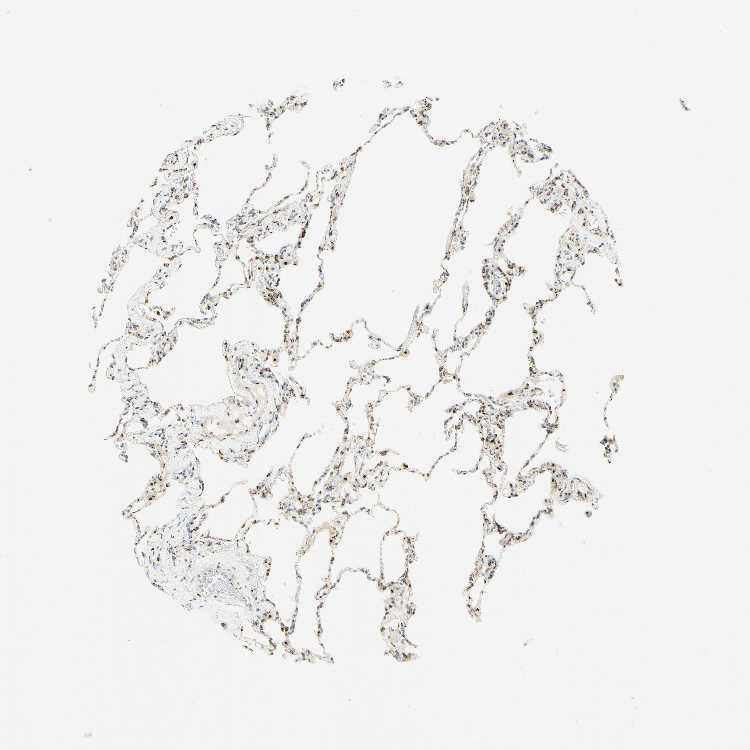

LUNG - Antibody stainingi

Antibody staining in the annotated cell types in the current human tissue is reported as not detected, low, medium, or high, based on conventional immunohistochemistry profiling in selected tissues. This score is based on the combination of the staining intensity and fraction of stained cells.

Each image is clickable and will lead to virtual microscopy that enables deeper exploration of all samples and also displays staining intensity scores, fraction scores and subcellular localization as well as patient and tissue information for each sample.

Antibody HPA011008Antibody HPA011555

Alveolar cells High-

Alveolar cells type I -High

Alveolar cells type II -High

Endothelial cells -Not detected

Macrophages HighHigh